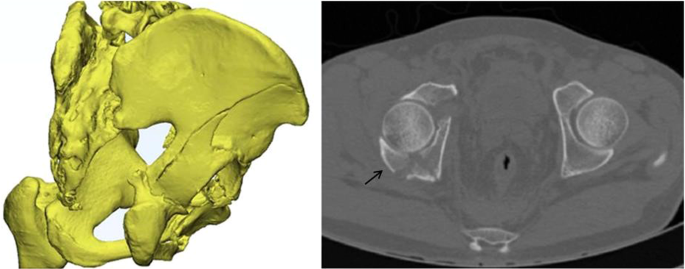

In 1964, Judet et al. introduced a classification scheme for acetabular fractures that is still in use1. In this classification system, posterior wall fractures constitute the most common of the elementary patterns, including isolated and associated fractures (transverse-posterior wall and posterior column-posterior wall fractures)2. These types of posterior wall fractures are all caused by the impact of the femoral head on the posterior wall of the acetabulum posteriorly3. Previous studies in the literature have adequately reported the treatment and prognosis of these types of posterior wall fractures, suggesting that anatomical reduction and internal fixation are key to achieving good outcomes, unless the hip remains stable4,5. However, in our clinical work, we found that both-column acetabular fractures are sometimes associated with posterior wall fractures (Fig. 1), which is not in the Judet and Letournel classification system and represents 34.8% of cases, according to the literature6. In addition, the injury mechanism is the transmission of trauma medially to the anterior column, posterior column and quadrilateral plate. As a result, the posterior wall is pulled anteriorly by the hip joint capsule5,7.

CT scan digital imaging communication in medicine (DICOM) imaging files were used as input data for the Mimics 20.0 program (Materialise Inc., Belgium) to measure and compare the characteristics of posterior wall fragments between the two groups.

Articular surface area of the fracture fragment: The injured femoral head was removed on the CT reconstruction in Mimics 20.0. The 3D reconstruction was then converted by 3-Matic 12.0, and the articular surface area of the fracture fragment was measured (Fig. 4).